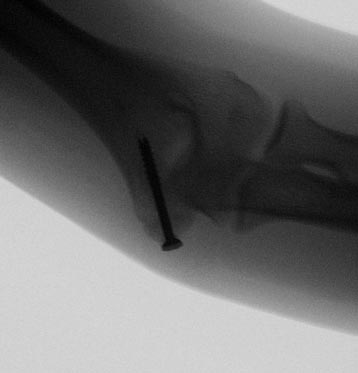

Post-Surgery

Repair of Non-Union With Plates and Screws

Repair of Condyle Fracture With Screw